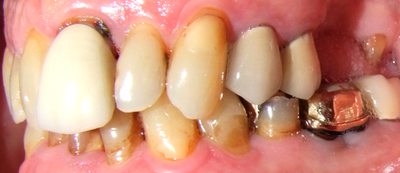

31284 Hg%2Bwb Dd4cfe8c

Hier "in Echt" bei einem Patienten mit chronischer Prostatitis...

Beim Zahnarzt sei alles "okay"...